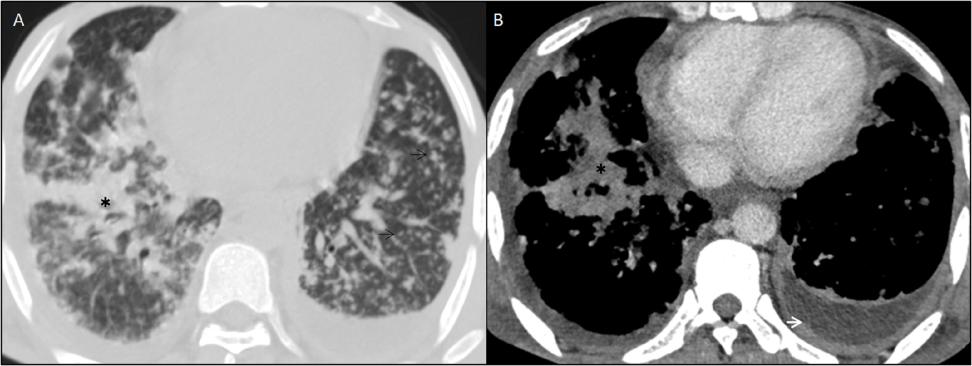

The scan was done on 128 slice Siemens CT scan machine, which revealed moderate hepatomegaly with liver measuring 17.5cm in craniocaudal dimension (Figure 1A). There were multiple conglomerated and enlarged lymph nodes with internal low attenuating areas (signify necrosis) observed in pre-para aortic, aortocaval and mesenteric regions (Figure 1B), largest measuring (20x11)mm in the right iliac fossa. The spleen was also enlarged with numerous tiny hypodense peripherally enhancing lesions diffusely scattered in its parenchyma (Figure 2). A minimal amount of free fluid was noted in the peritoneal cavity. The CT scan also demonstrated multiple centrilobular nodular densities arranged in linear branching patterns forming tree-in-bud appearance and patchy areas of consolidations in the limited scan of the bilateral lung fields (Figure 3A). Mild right-sided pleural effusions and left-sided empyema were also noted (Figure 3B).

Figure 1 Contrast enhanced computed tomography scan, venous phase in coronal plane, (A) shows multiple conglomerated, peripherally enhancing lymph nodes with central low attenuation in mesentery adjacent to mesenteric vessels (white arrow). (B) shows mild enlargement of the liver and spleen (craniocaudal length measures approx 17cm and 16cm respectively). Numerous tiny hypodense peripherally enhancing lesions are seen diffusely scattered insplenicparenchyma (white arrow).

Figure 3 CECT of bilateral lower hemithorax in axial planes (A) Lung window, shows multiple tiny centrilobular nodular opacities in bilateral lung fields (black arrows) forming “tree-in-bud appearance” and patchy consolidation in right lower lobe (black asterisk) signifies active pulmonary tuberculosis. (B) Soft tissue window reveals thickened and enhancing left pleural linings with fluid collection in pleural space forming “split pleura sign” suggesting empyema.